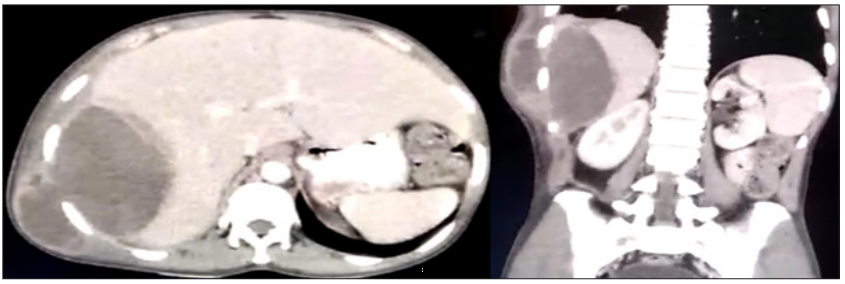

A 35-year-old gentleman presented with a complaint of hemoptysis for last 1 month and fever for last 2 days. He complained occasional pain in the right upper quadrant of the abdomen. On examination a lump has been noted in the right flank which appeared to be soft, fluctuant, non-tender (Figures 1 & 2). The lump was not pulsatile but was slightly moving with respiration. On investigation by a CECT abdomen (Figure 1) a hypoechoic lesion in the right lobe of liver was found which was communicating beneath the skin. A diagnosis of amebic liver abscess was made. On aspirating the abscess anchovy-sauce like pus was obtained. However, the pus was sterile i.e. no trophozoite or cyst was found. He received metronidazole and the pus was aspirated and drained. Amebic liver abscess can very rarely present in such a fashion. If it presents in such a fashion a provisional diagnosis can be made from CT scan since it doesn’t contain any septation and has a thickened wall. The characteristic pus is anchovy-sauce colored. The possible explanation of hemoptysis is rupture is a broncho-hepatic fistula. Other modalities that could be used for diagnosing amebic liver abscess can be serological testing of antiamebic antibodies in serum.1 The drawback of estimating antibodies against total amebic antigen is that in a highly endemic area often patients may remain seropositive for years after infection and antibody response to Gal/GalNAc adherence lectin, on contrary, is much shorter lived and present in acute amebiasis [1].

Figure 1: CECT Abdomen showing a hypoechoic lesion in the right lobe of liver communication beneath the skin. (Left hand side shows transverse section and right hand side shows coronal section of abdomen).